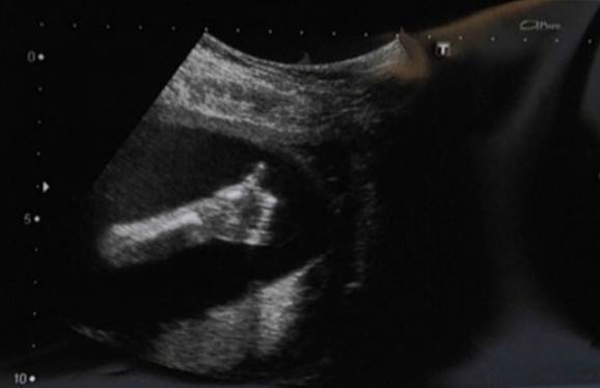

Но в кабинете УЗИ-диагностики ее ожидал сюрприз, которого она при всей своей богатой фантазии даже представить себе не могла. Сигнал о том, что с ребенком все в порядке дал сам ребенок. На экране было отчетливо видно, как малыш сложил кулачок и поднял вверх указательный палец, сделав всем хорошо знакомый жест. Потрясенная мама от радости расплакалась, а проводивший УЗИ-диагностику врач, напротив, расхохотался.

"Малыш определенно давал мне понять, что с ним все в порядке, - улыбается теперь Донна Сойер. - Он как бы говорил: "Не бойся, мама, у меня все ОК". Врач у меня попросила сделать копии УЗИ-снимков. Она считает, что эти сканы надо повесить в кабинете - они будут поднимать настроение у всех беременных женщин".